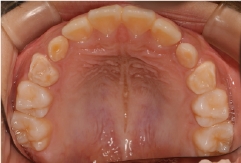

症例1

11歳女子

治療前

治療後

| 施術名 | 拡大床にて治療 |

|---|---|

| 施術の説明 | 協力的な患者様で治療がスムーズに進んだ。 |

| 施術の副作用(リスク) | 歯の交換期だったので、後続永久歯の萌出を妨げないように注意した。 |

| 施術の価格 | 33万円 |